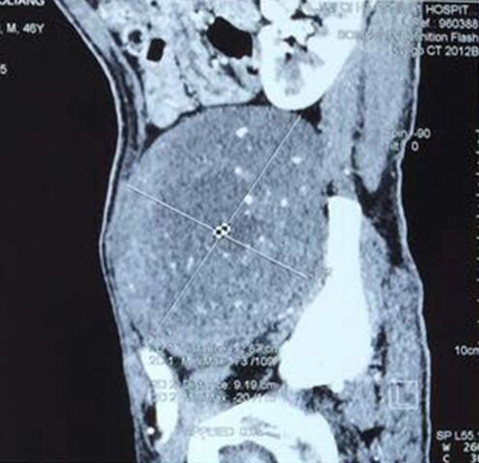

左侧盆腔椎体旁腹膜后巨大肿物切除

赵先生45岁,于2015年7月发现左侧腹部有一无痛性肿物,约鸡蛋大小,赵先生认为这肿物不痛不痒,就没重视。可随着时间推移,肿物逐渐增大,李先生出现左下肢疼痛、麻木的症状,包块增长至约拳头大小,疼痛明显加重,甚至无法入睡,严重影响李先生生活质量,仅半年时间,体重减轻10kg,在外院行增强CT检查示:“左侧腹膜后占位,考虑间叶源性肿瘤可能性大”。为求进一步诊治,李先生多方打听来我院骨外一科就诊。确诊后,白玉江主任决定为此其行肿物切除术。术中见腹外斜肌下方肿物,手术难度及风险极大,经过两个小时的手术,最终将15×10×10cm3巨大肿瘤完整切除。术后病理回报:粘液性脂肪肉瘤。术后一个月及两个月随访,患者左下肢疼痛无复发。

手术难度:由于患者有肿瘤病史,且此重物巨大在盆腔内,无活动度,手术难度极大,因肿物巨大与周围组织粘连,手术时间较长,并极有可能造成输尿管、腹膜、肠管、神经的损伤;该肿瘤恶性可能性大,若侵犯周围组织,需扩大切除;其中最危险的是肿物在盆腔与左髂骨粘连且无活动度,若将其完整切除极有可能损伤盆底静脉丛,造成大量失血,引起失血性休克导致患者死亡。

入院后腹部MRI